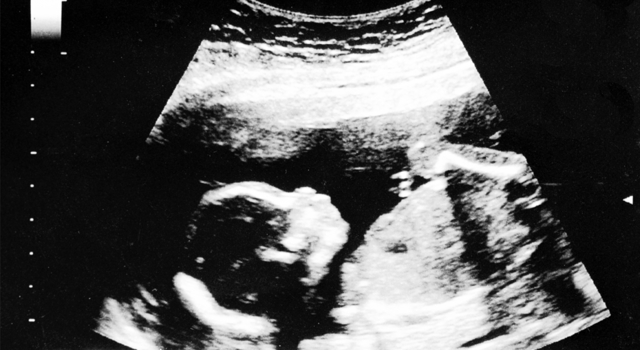

La grossesse - semaine 21

Embryon : 24cm / 440g

Durant cette vingt-et-unième semaine, bébé pèse 440g et mesure 24cm. Il s’exerce à la succion en suçant son pouce ! Les ongles et les cheveux continuent à pousser, et les poumons fonctionnent maintenant bien, même s’il respire encore irrégulièrement. Les yeux de votre bébé sont encore fermés. Par contre, il entend très bien, n’hésitez pas à lui parler !